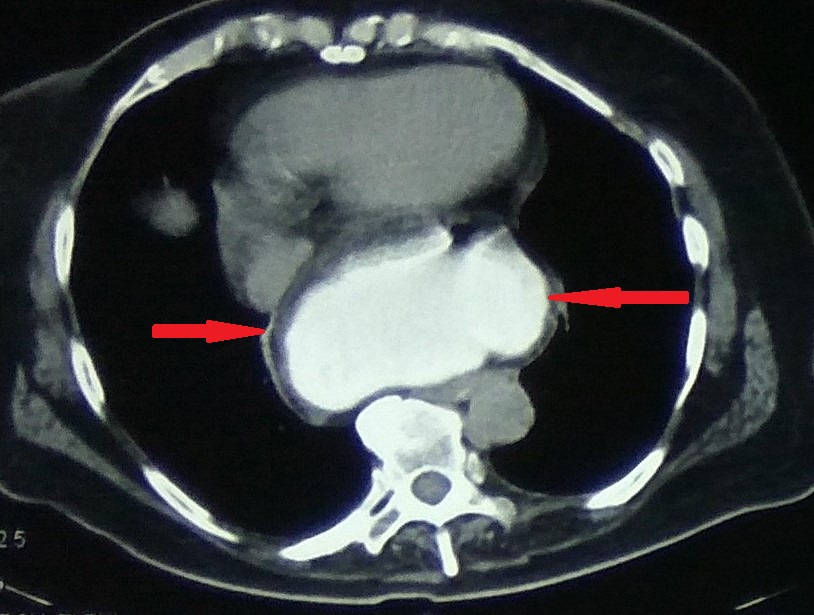

Different views of a double contrast-enhanced CT scan showing a left diaphragmatic hernia with an acute dilated stomach (Courtesy Dr. V. Penopoulos)